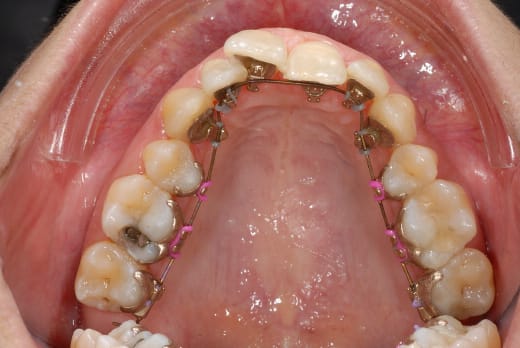

voilà mes p'tits, voilà tout l'or dont j'ai hérité :-)

vous trouvez pas que ça s'est aligné en bas? :-)

..et la carie sur la 16 ???

Le haut commence aussi à prendre forme...mais n'est ce pas un peu trop rapide?

Le fil il est en quoi ? (L'or n'est à mémoire de forme ?)

ben en or, enfin je crois! mais là c'est le tout début, donc fil souple....

mais parlons bimétallisme tant qu'on y est, regarde l'amalgame de ma 36....